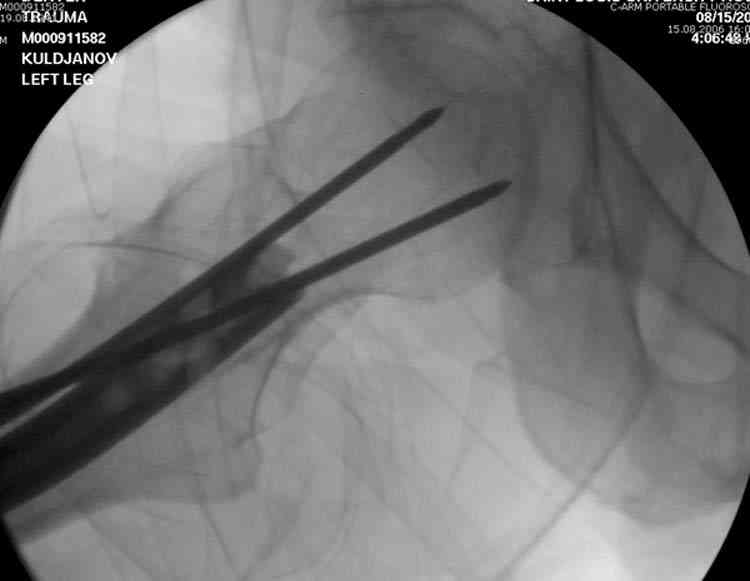

Здесь представлены снимки больного 65 лет, поступившего с диагнозом перелом

бедра после автоаварии.

В первый же день произведено антеградное штифтованием DePuy Trochanteric Nail.

На второй день (7) обнаружен пропущенный перелом,

сделаны Компьютерная Томограмма

и проведены шурурпы через и спереди штифта без удаления.

Послеоперационные снимки